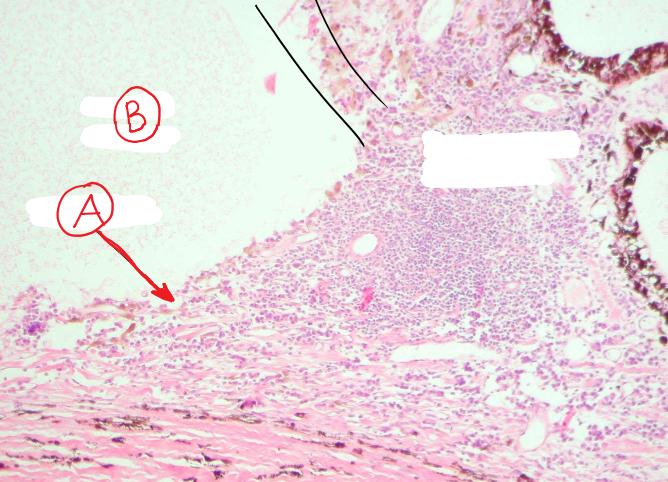

12

What is labeled here?

A.

B.

A

A. Ciliary cleft

B. Anterior chamber